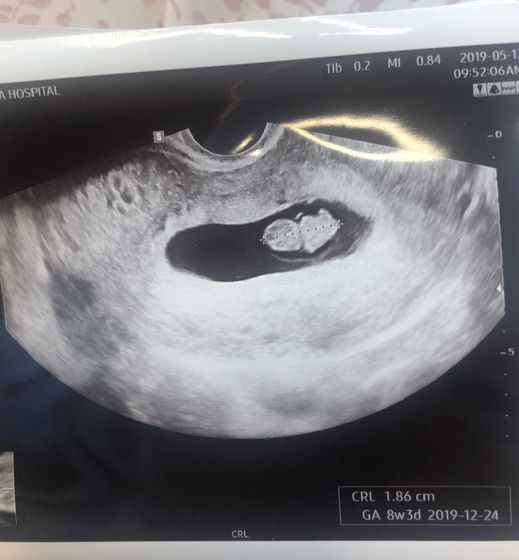

А тут такая красота ? Прям шею видно ? ЧСС 160 уд/мин.

Узи делаю раз в неделю и каждую неделю он мне говорит что малыш старше на три дня)) Так что сейчас 8нед и 3 дня))